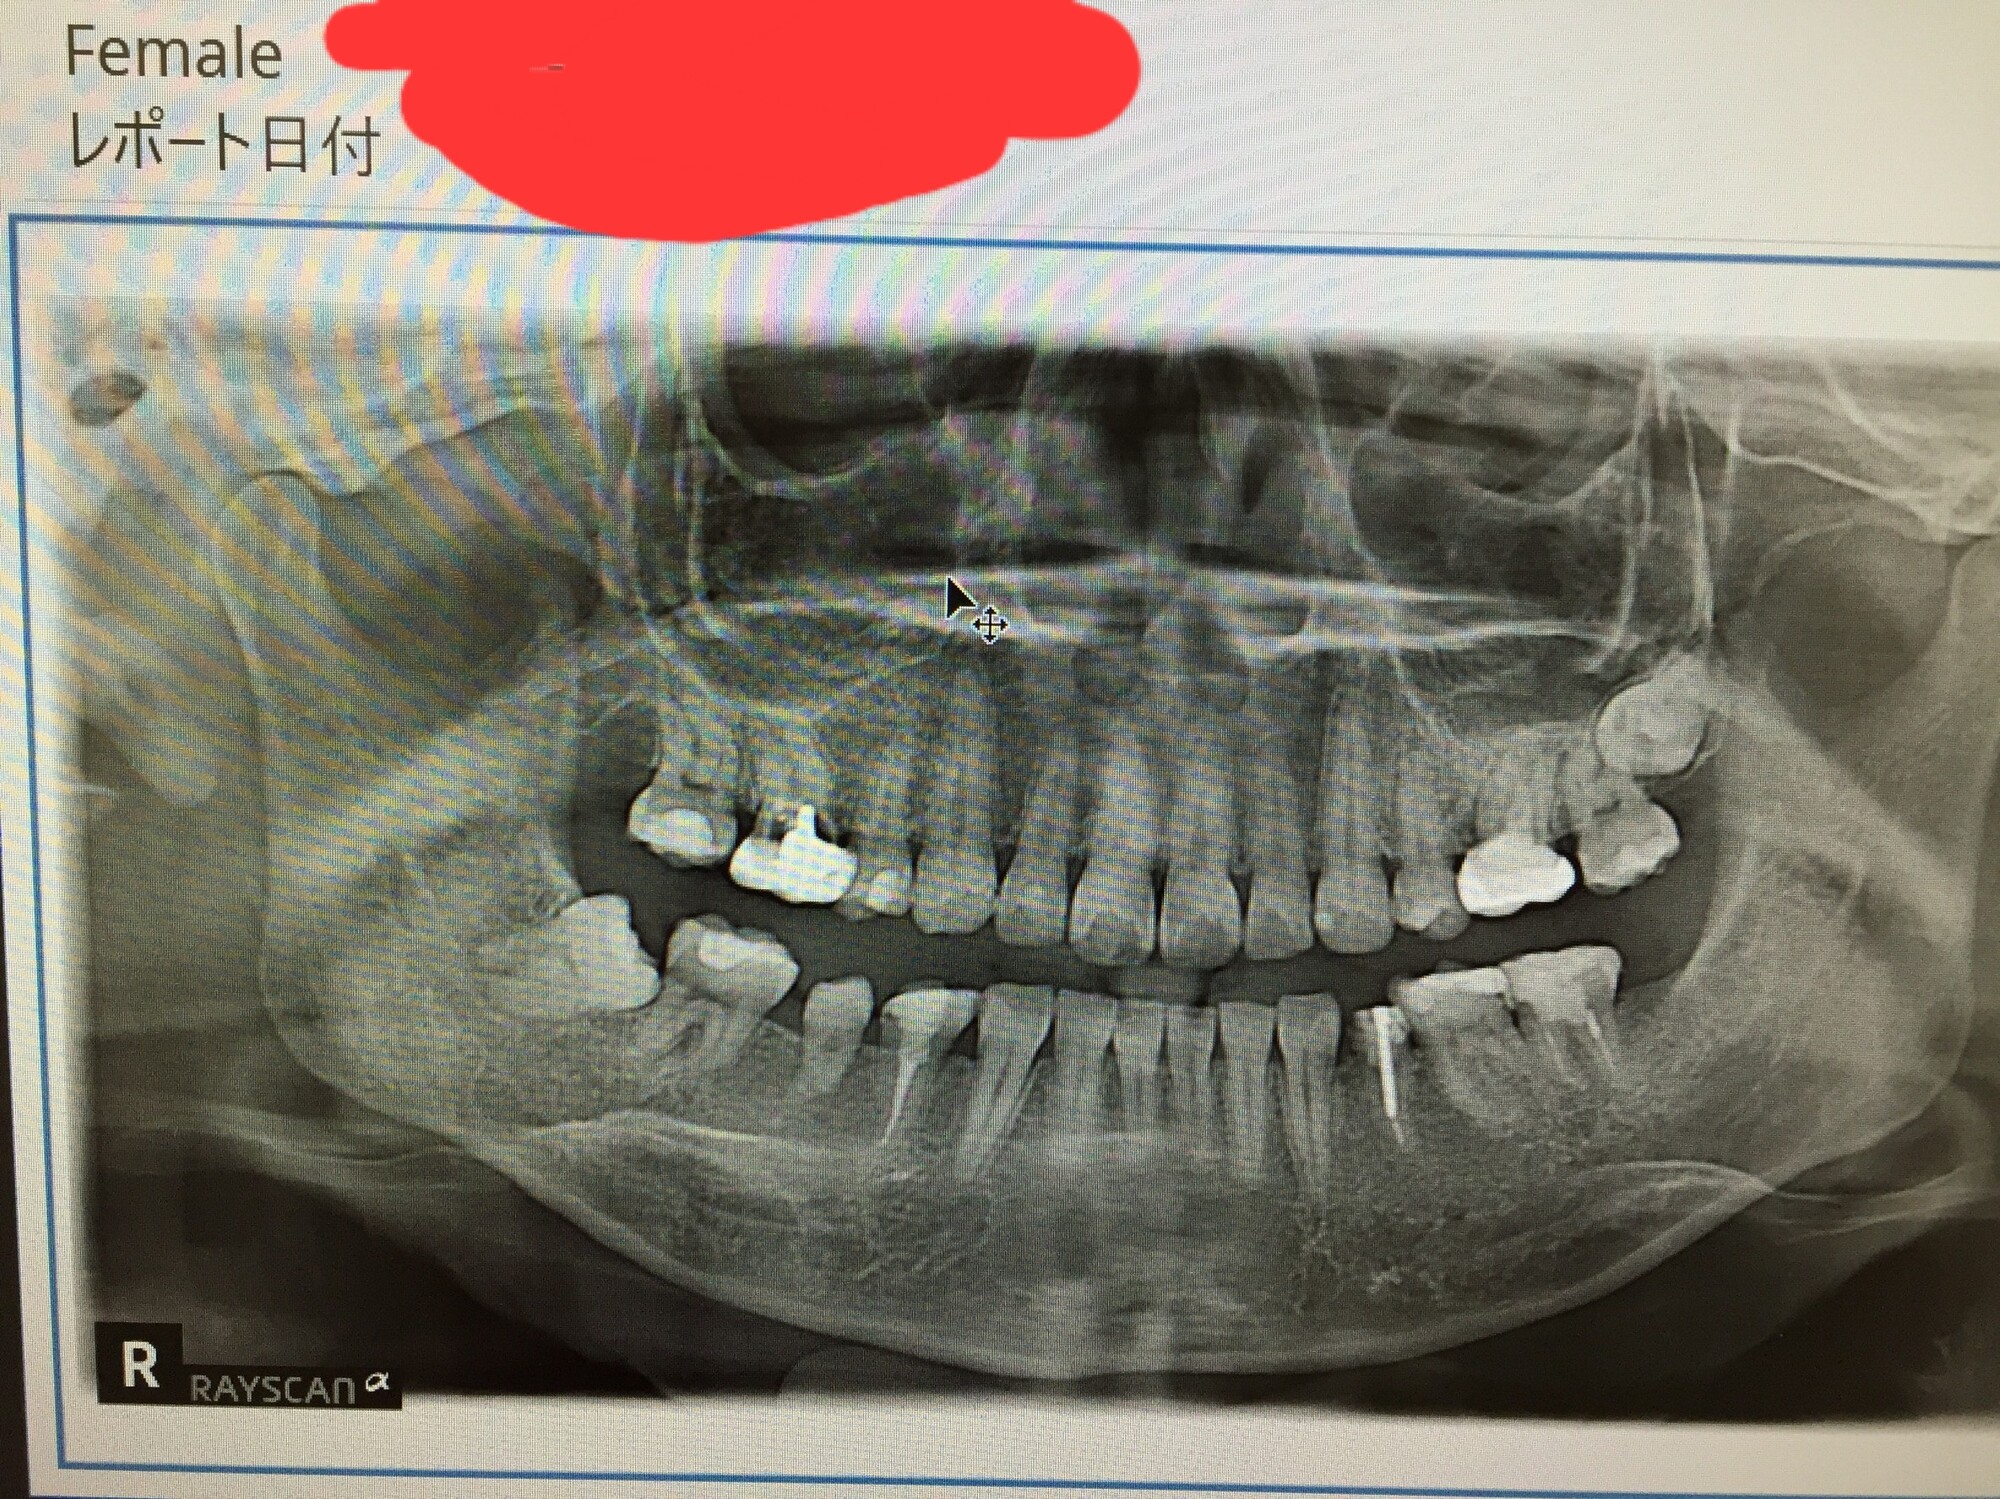

術前

歯の移植手術の前には、患者の口腔状態や全身の健康状態を評価するための検査が行われます。口腔内のレントゲン撮影やCTスキャンを用いて、顎の骨の密度や形状を評価し、移植に適した歯の選択や手術計画を立てます。また、患者の歯周病の状態や口腔内の感染症の有無も確認されます。